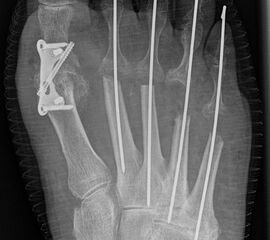

Deutlich bessere Ergebnisse wurden erreicht durch eine Kombination der OP nach Tillmann mit einer Arthrodese des Großzehengrundgelenks oder auch einer Lapidus-Arthrodese 611. Dies wurde bereits 1956 durch Vainio empfohlen, hat sich aber erst in diesem Jahrtausend flächendeckend durchgesetzt 121314.

Abschließend erfolgt die temporäre K-Daht Fixation sämtlicher Kleinzehen in achsgerechter Stellung. Die Strecksehnen werden in Verlängerung vernäht.